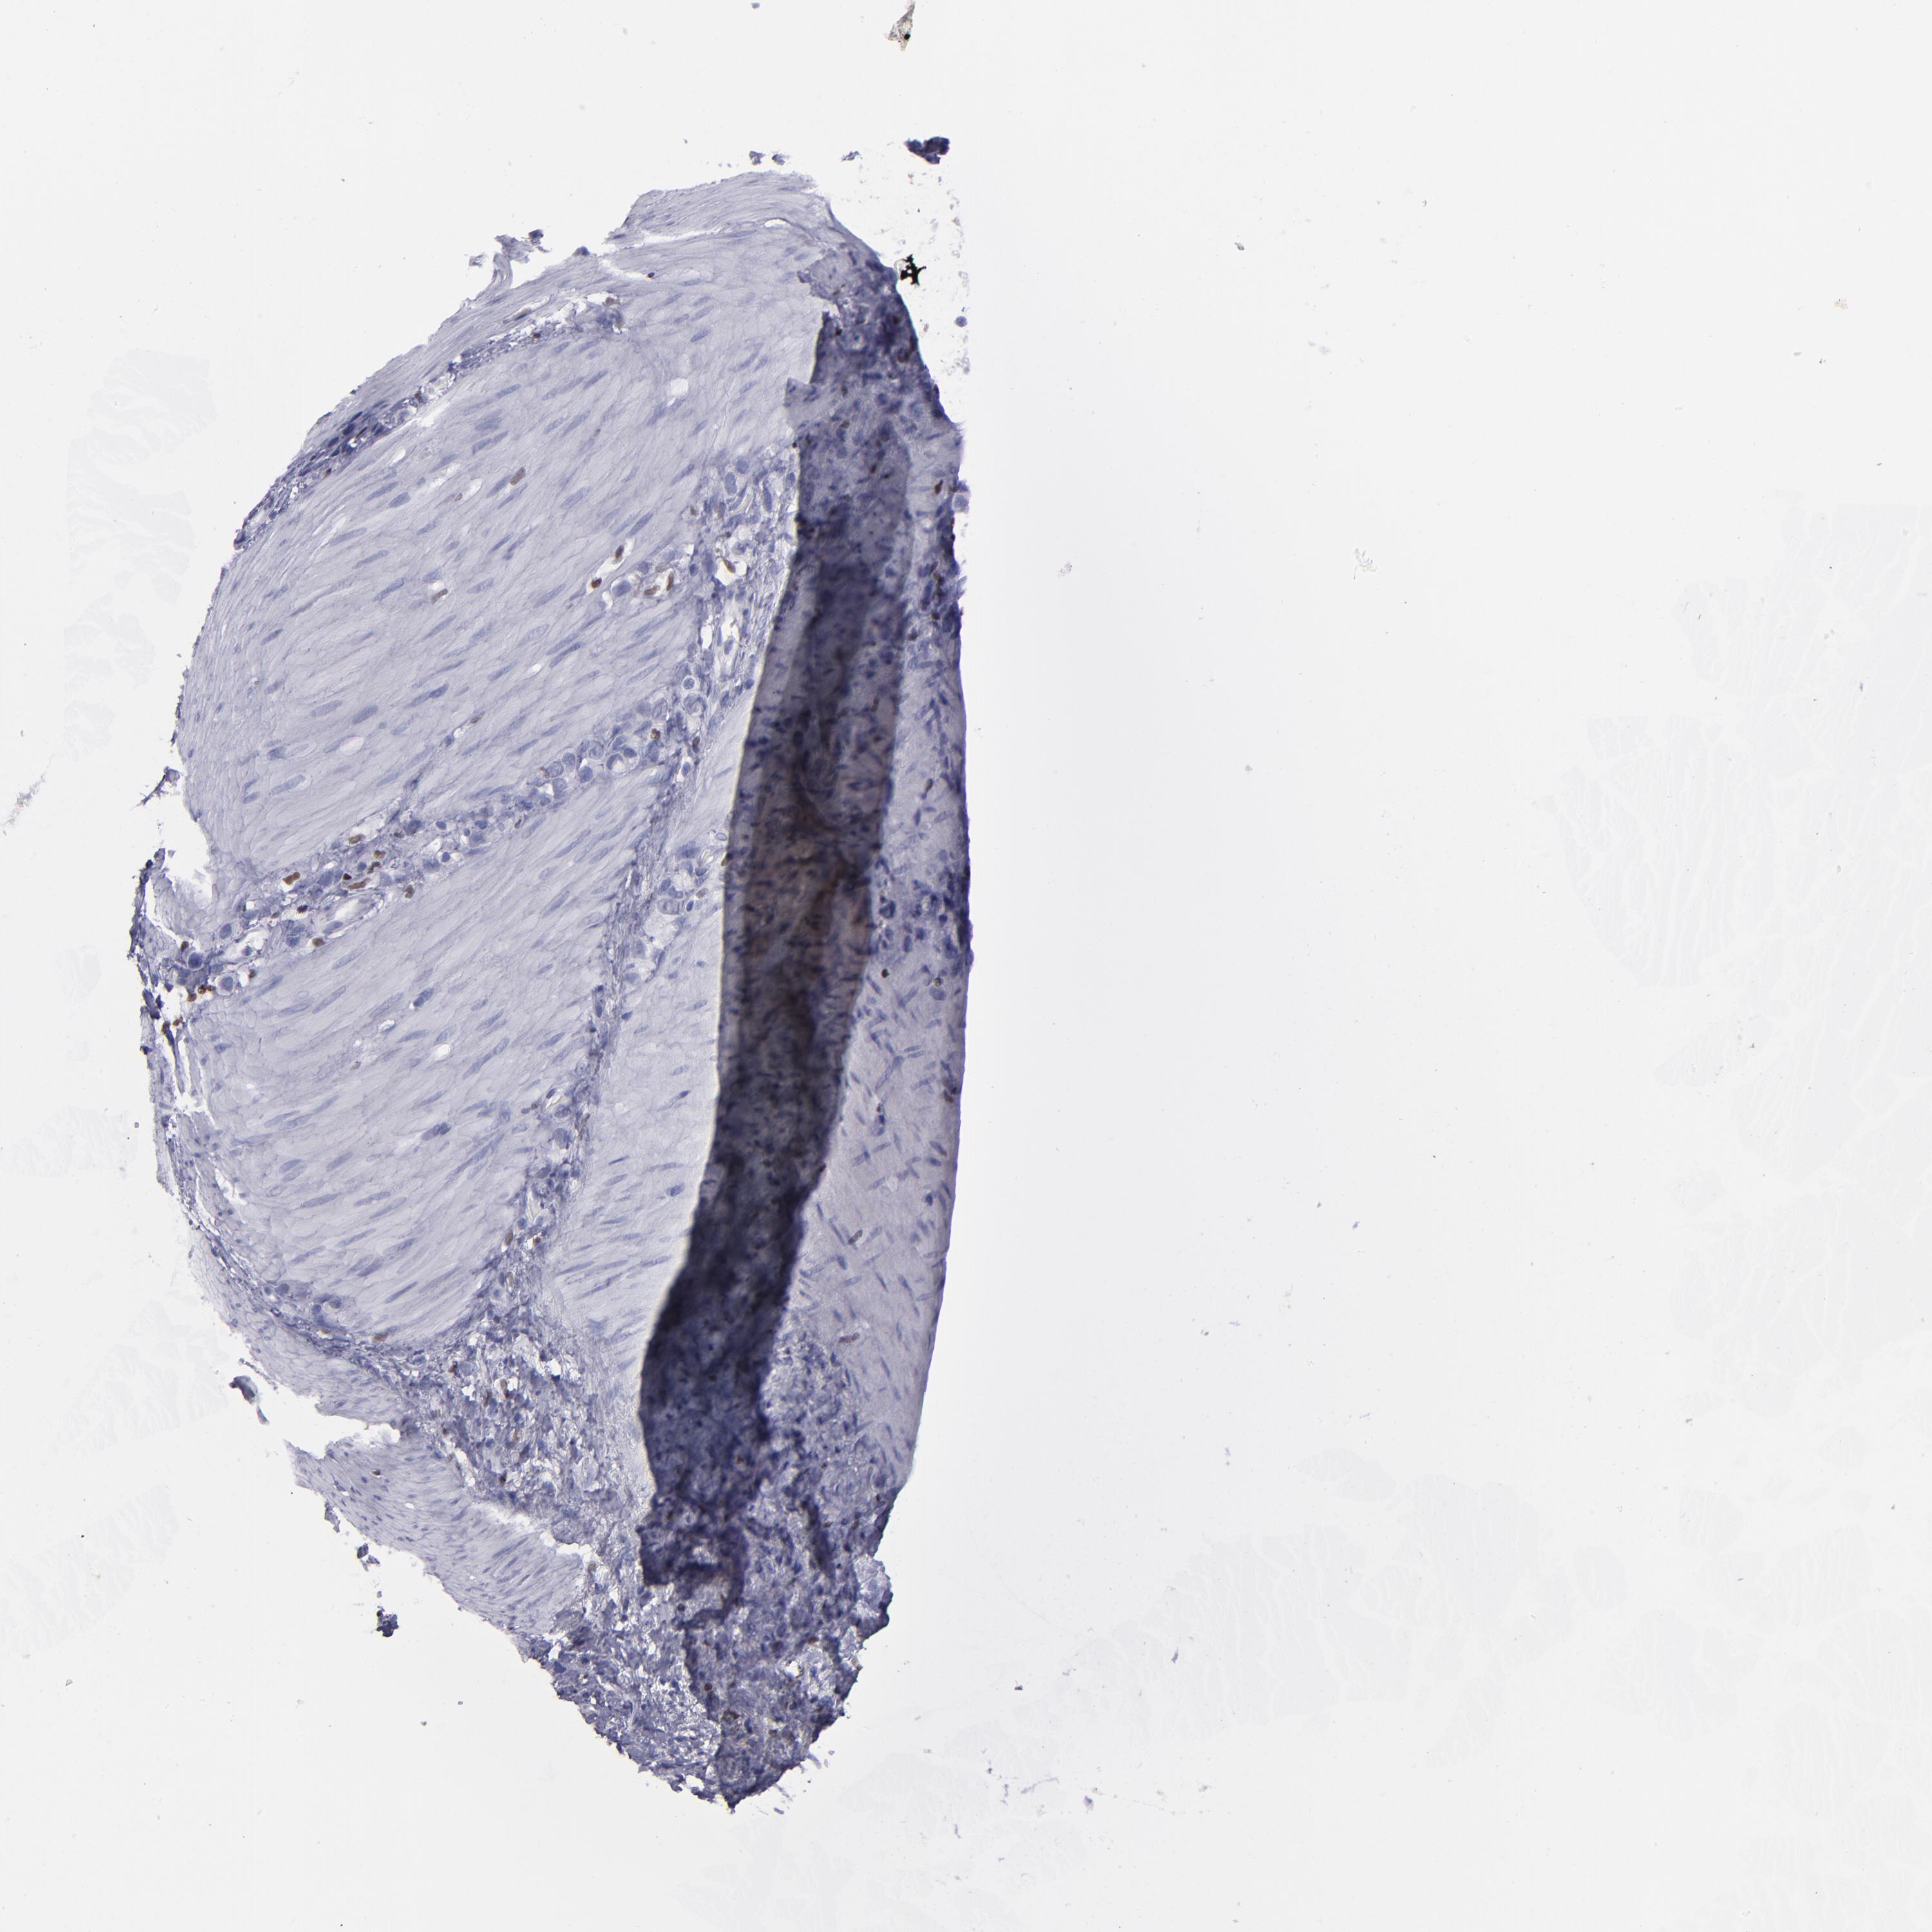

STOMACH CANCER - Protein expressioni

A mouse-over function shows sample information and annotation data. Click on an image to view it in a full screen mode. Samples can be filtered based on level of antibody staining by selecting one or several of the following categories: high, medium, low and not detected. The assay and annotation is described here.

Antibody stainingi

Antibody staining in the annotated cell types in the current human tissue is reported as not detected, low, medium, or high, based on conventional immunohistochemistry profiling in selected tissues. This score is based on the combination of the staining intensity and fraction of stained cells.

Each image is clickable and will lead to virtual microscopy that enables deeper exploration of all samples and also displays staining intensity scores, fraction scores and subcellular localization as well as patient and tissue information for each sample.

Antibody HPA002267

Antibody HPA002531

Antibody CAB013480

Staining

High

Medium

Low

Not detected

Intensity

Strong

Moderate

Weak

Negative

Quantity

>75%

75%-25%

<25%

None

Location

Nuclear

Cytoplasmic/membranous

Cytoplasmic/membranous,nuclear

Adenocarcinoma, NOS

Adenocarcinoma, High grade